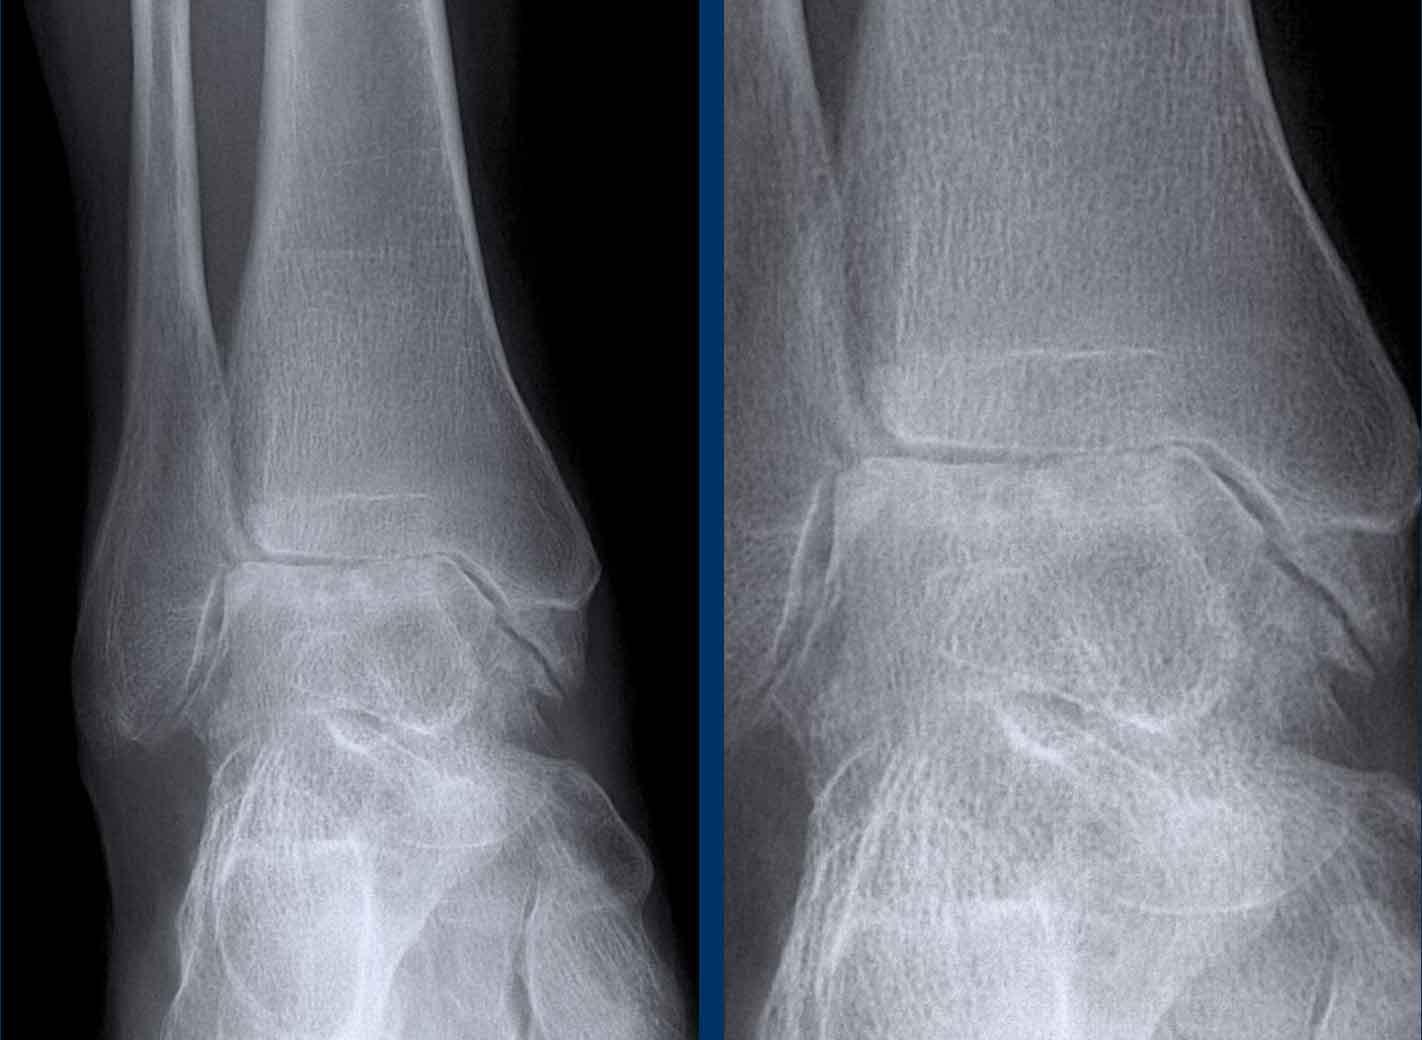

Hình ảnh khớp cổ chân của bệnh nhân hemophilia.

Các dấu hiệu bao gồm:

- hẹp khe khớp đối xứng lan rộng,

- hình thành nang xương dưới sụn

- thay đổi dạng bào mòn xương

Bệnh khớp do hemophilia giai đoạn cuối

- hẹp khe khớp đối xứng

- tràn dịch khớp

- viêm khớp thoái hóa thứ phát với gai xương

Mặc dù bản thân các dấu hiệu này không đặc hiệu, có thể nhận thấy sự tương đồng giữa tất cả các trường hợp nêu trên.